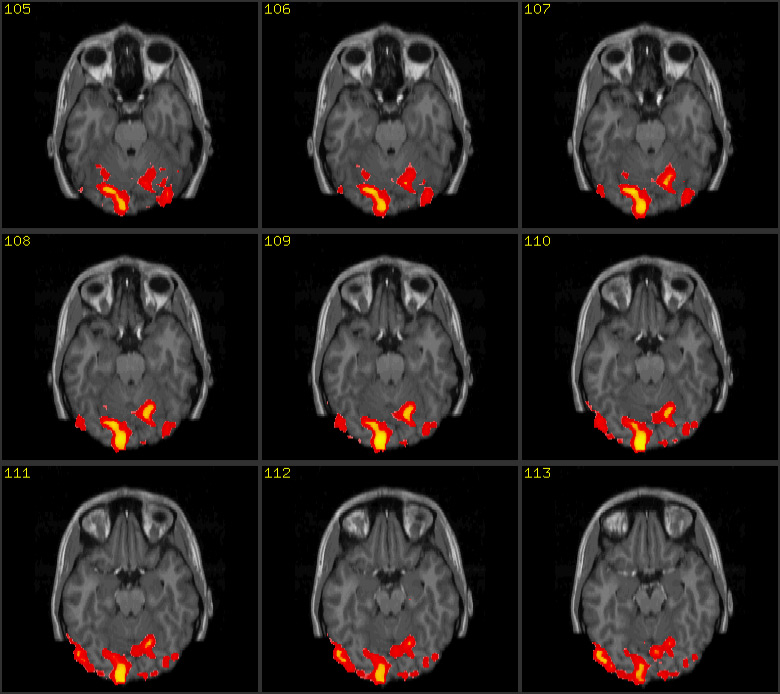

The illustration shows two images: the first one is a scan of the brain

obtained with Magnetic Resonance Imaging (MRI), the second is its functional

version (fMRI). MRI is a non-invasive scientific technique that generates

images of the body for diagnostic and research purposes. Along with its

functional version, MRI has been extensively applied to studies of brain

anatomy and cognitive functions, enabling researchers to detect and measure

the neuronal activity in almost real time. By showing the human brain at work,

brain scans are presented in the wider public arena and, specially, in the

media, as evidence of conditions of normality or illness that prompt us to

reshape our concept of personal identity (Dumit 2004).14

Brain scans embody both image traditions

that historian of science Peter Galison individuated within the field of

physics: the first tradition, called logical, substitutes the notion of the

image with the notion of statistical projection of data and digital

information; the second tradition, called image, describes images as natural,

illusionary or mimetic. According to this second tradition, images ‘preserve the form of things as

they occur in the world’ (Galison, 1997, 807). Brain scans function as authoritative

visual objects that are part of a multi-layered ensemble of networked

techniques and technologies (both analogical and digital) and human mediations,

embodying the logic of the database (de Rijcke and Beaulieu, 2014) and being

more the statistical projections of data rather than representations.

Therefore, brain scans can be aptly called image-data.